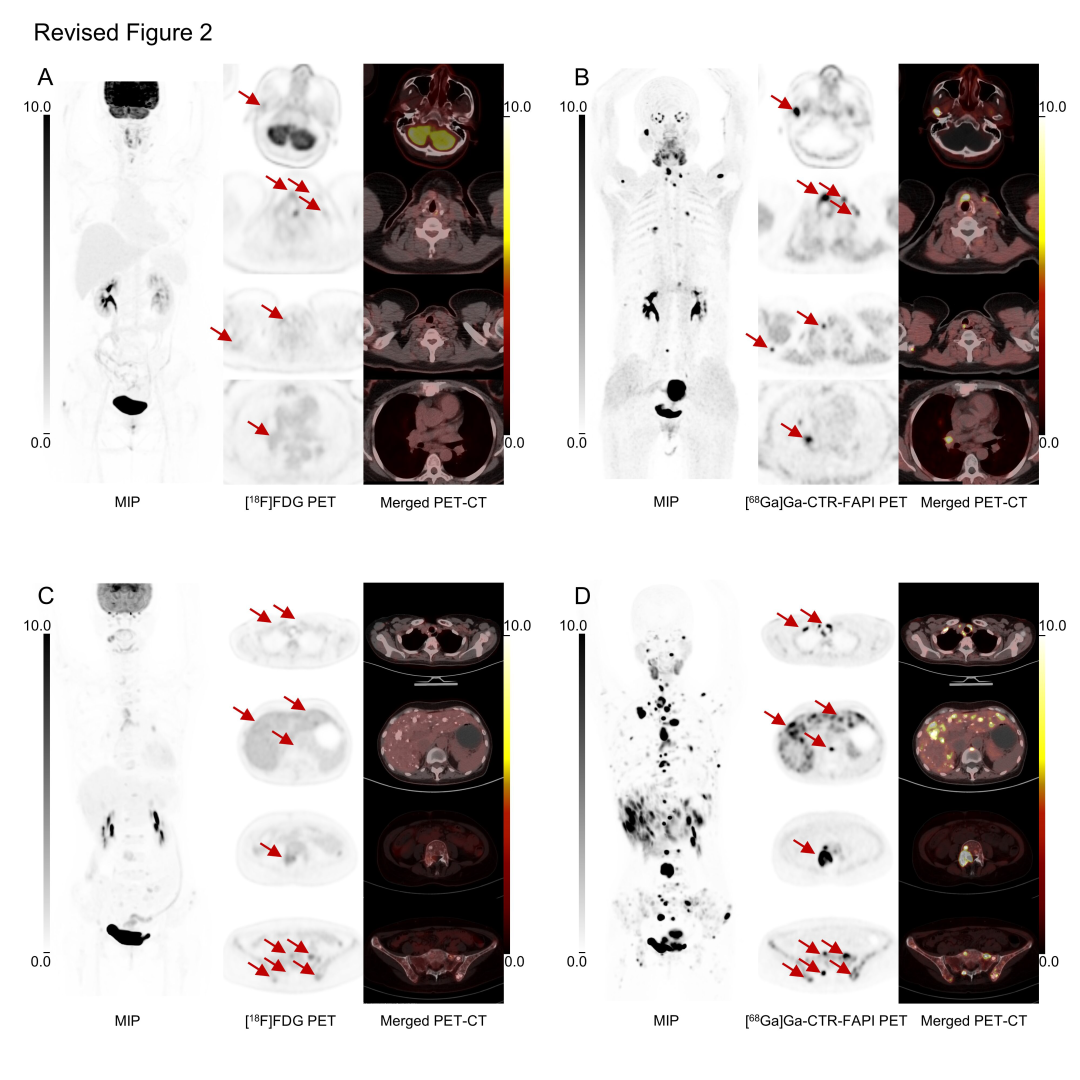

2024年10月,由中国医学科学院肿瘤医院头颈外科、北京大学肿瘤医院核医学科、北京昌平实验室及北京协和医院核医学科共同在《Cancer Discovery》上发表研究,首次在临床层面验证了基于共价策略的核药CTR-FAPI在甲状腺髓样癌(MTC)诊疗中的价值。研究表明,[68Ga]Ga-CTR-FAPI PET/CT显著提升了MTC病灶的检出灵敏度与定位精准度,尤其在常规[18F]FDG显像阴性的转移灶中展现出压倒性优势,为术前分期、手术边界判定、复发监测及治疗决策提供了决定性影像依据,彻底重塑了这一罕见且预后凶险疾病的临床管理路径,将MTC诊疗带入真正意义上的精准医学时代。